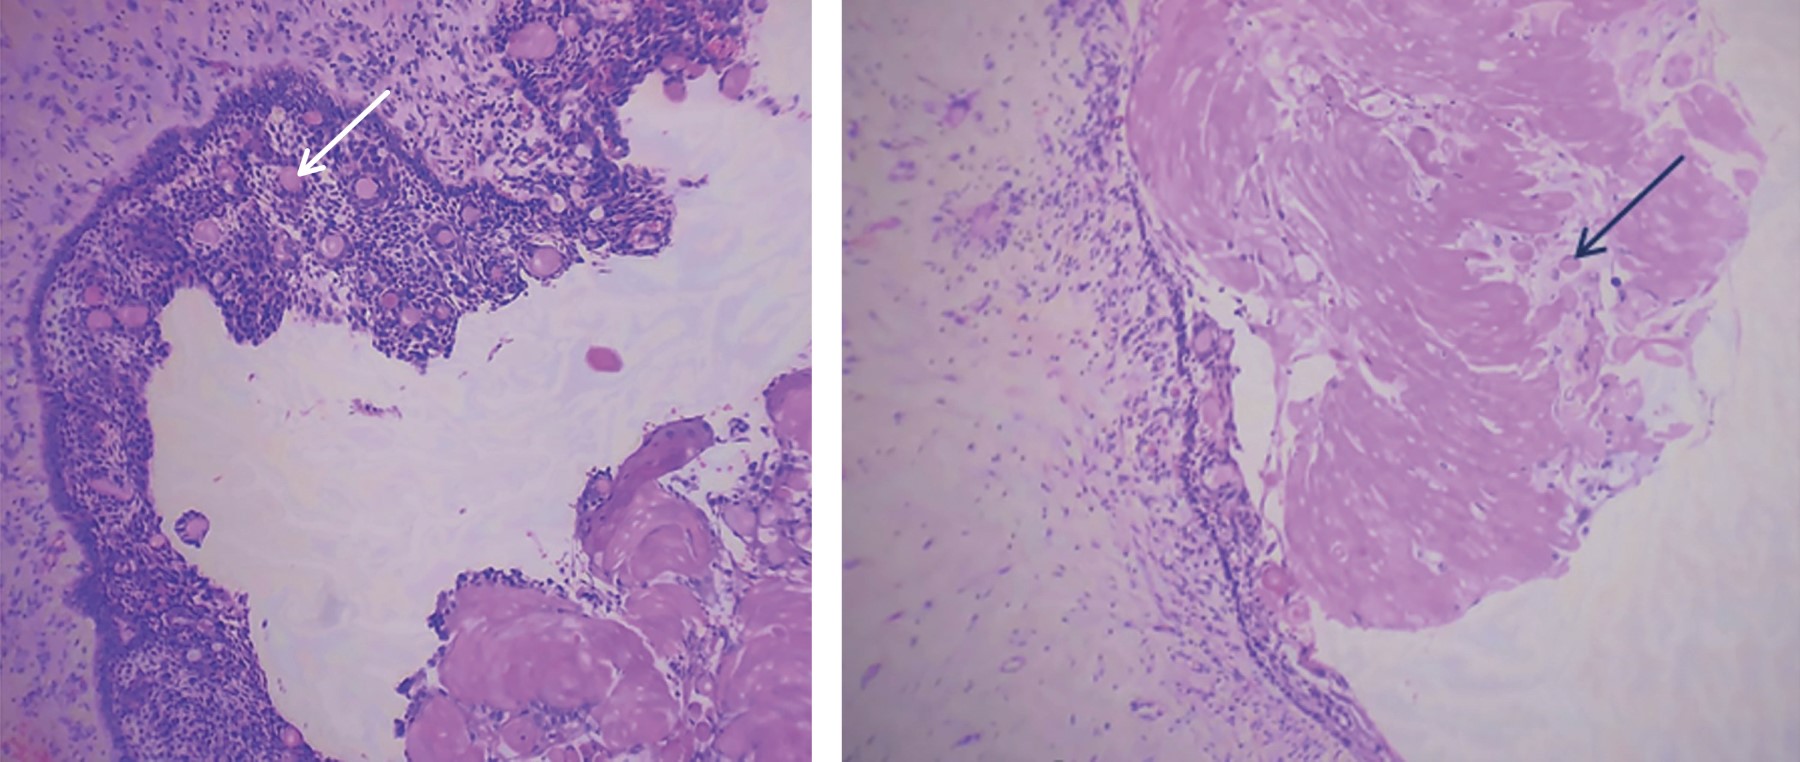

The calcifying odontogenic cyst is defined as a cystic lesion of benign origin originating from epithelial remains during odontogenesis, it presents as an asymptomatic and slow growthing lesion, which affects the anterior region of the mandible and the maxilla, it is frequent in young adults of the third to the fourth decade, without predilection for gender. It is rare, constituting only 0.37% to 2.1% of all odontogenic cysts and tumors. 65% occur in the incisor region of both jaws and approximately 20% are associated with an odontoma. Histologically, its generally composed of a cystic cavity with a fibrous capsule lined with odontogenic epithelium. The typical microscopic feature of this lesion is the presence, in varying numbers, of aberrant anucleated epithelial cells, called "ghost cells". The treatment is enucleation. We present the case of a 20-year-old male with a diagnosis of Gorlin's cyst in the left maxillary sinus and surgical treatment that consisted of enucleation of the lesion

Figure 1

Figure 2